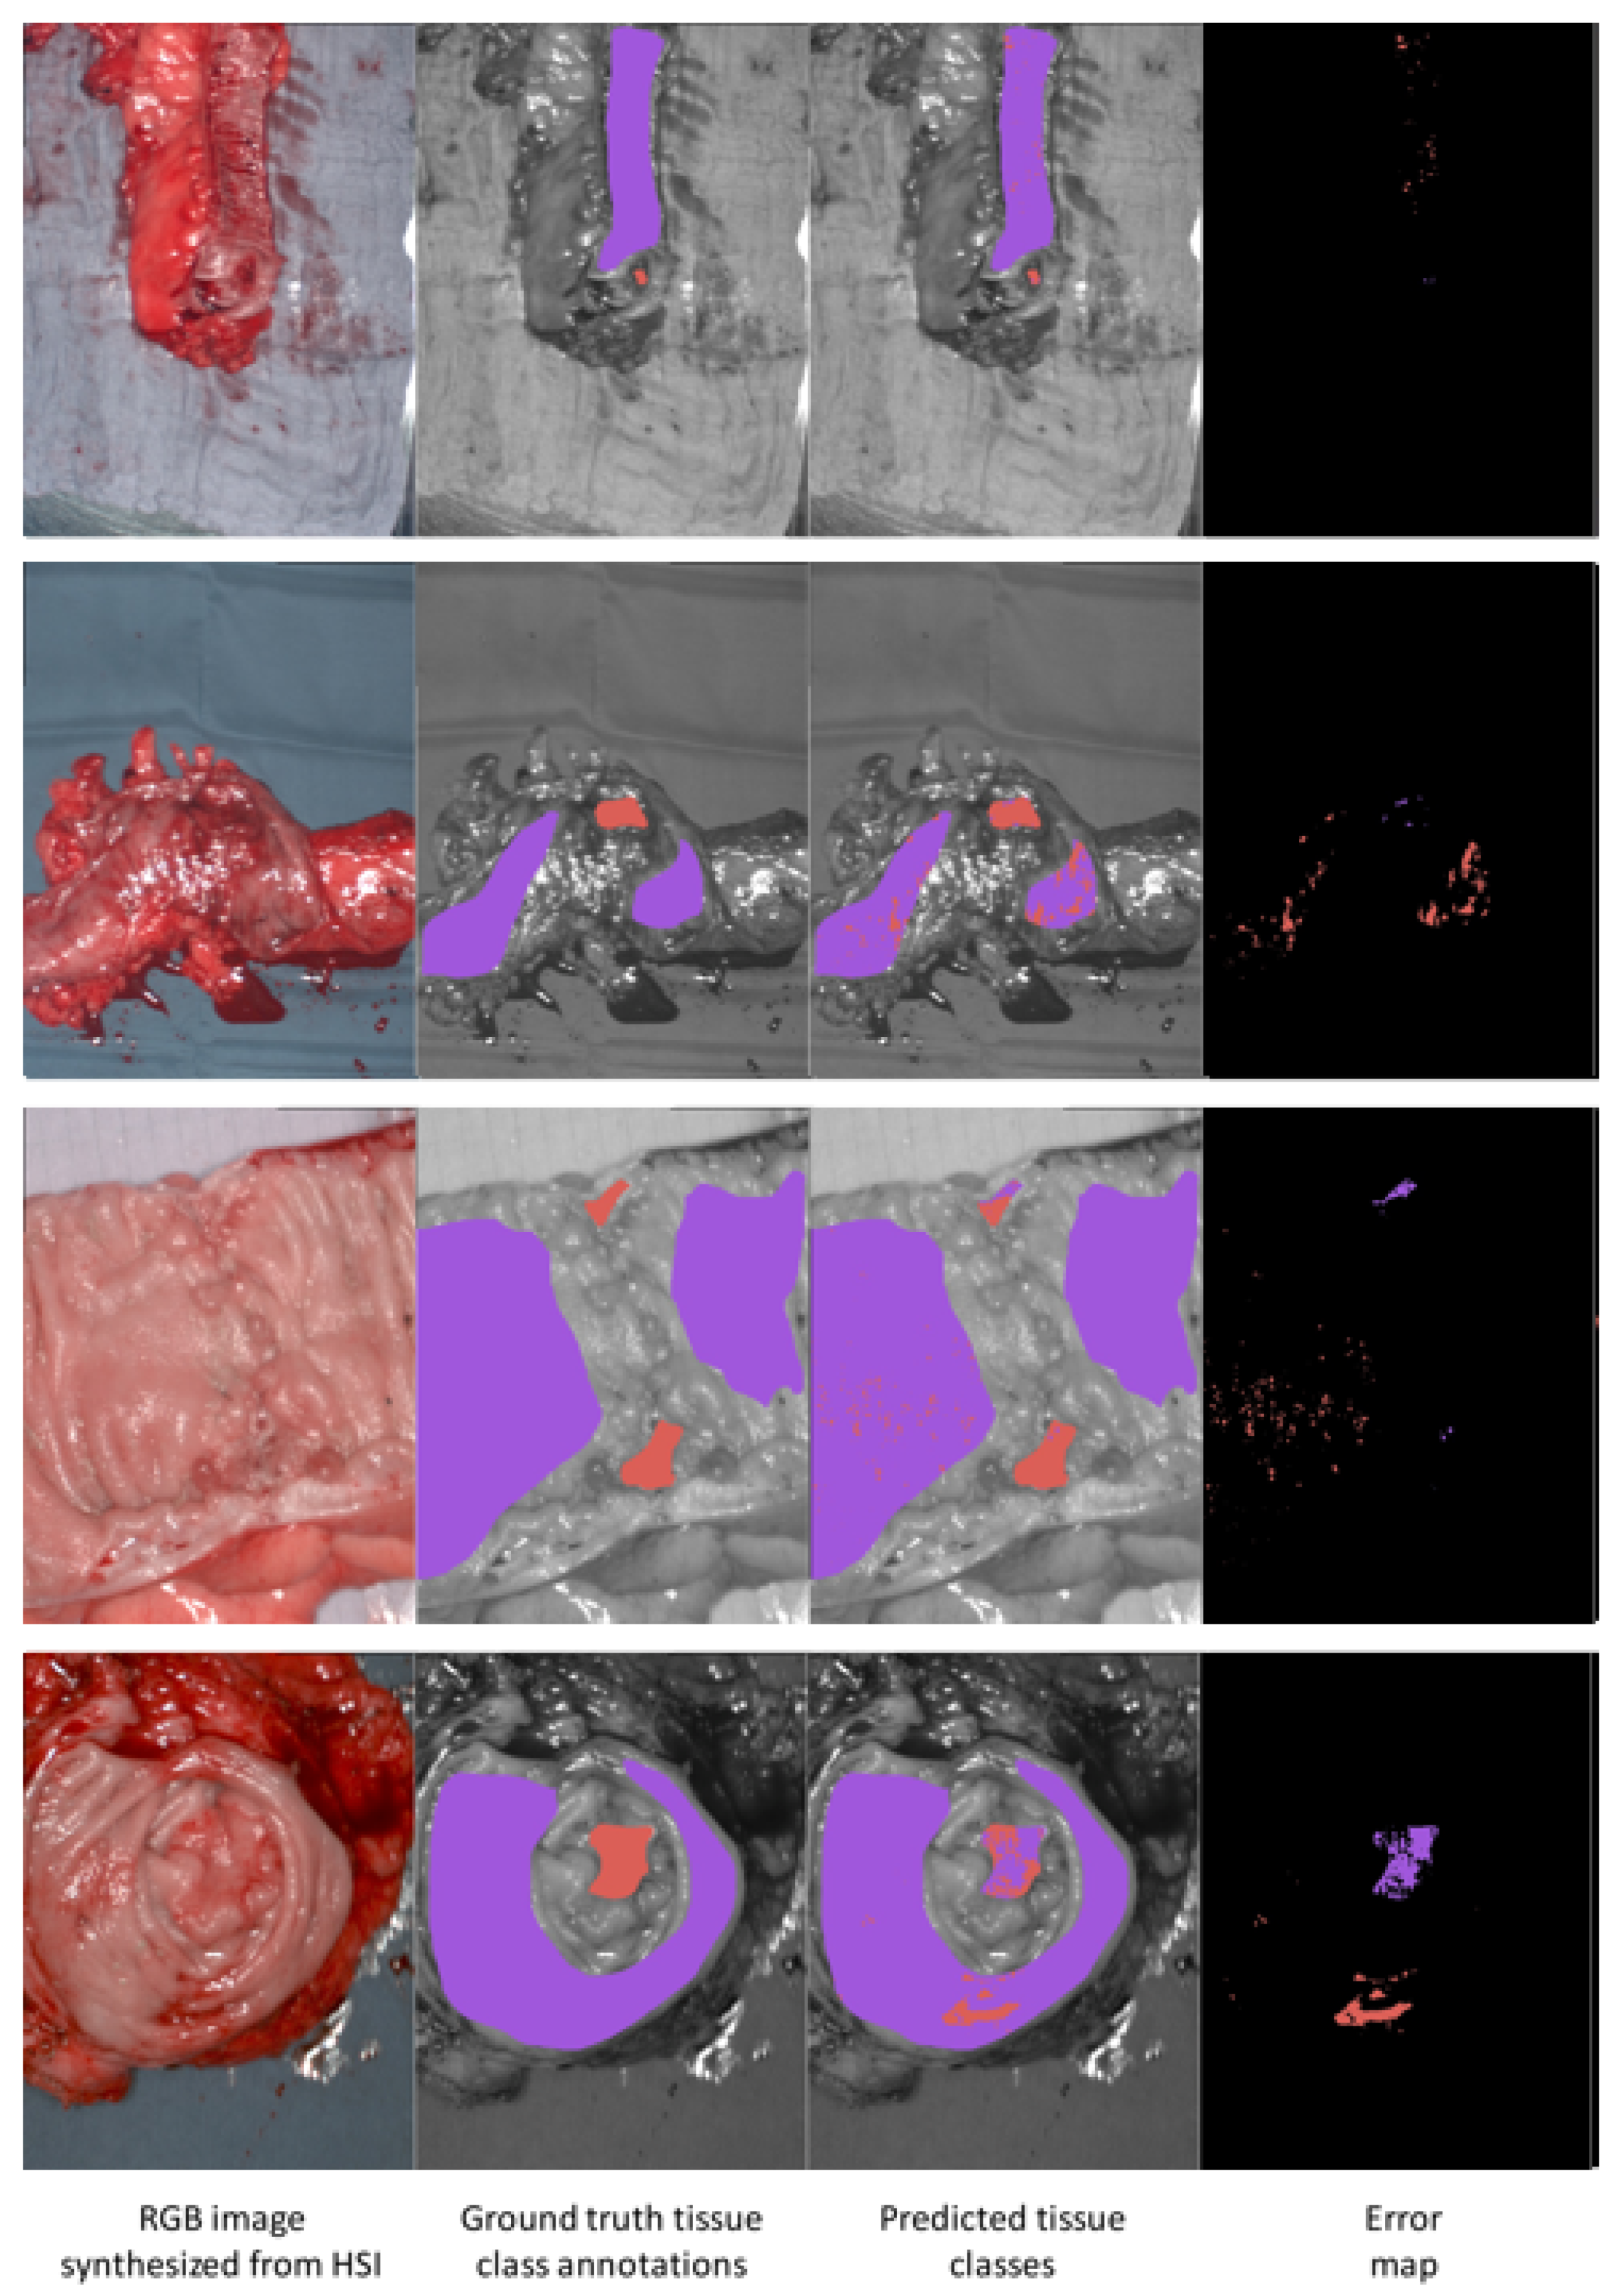

3.5. Results Visualization